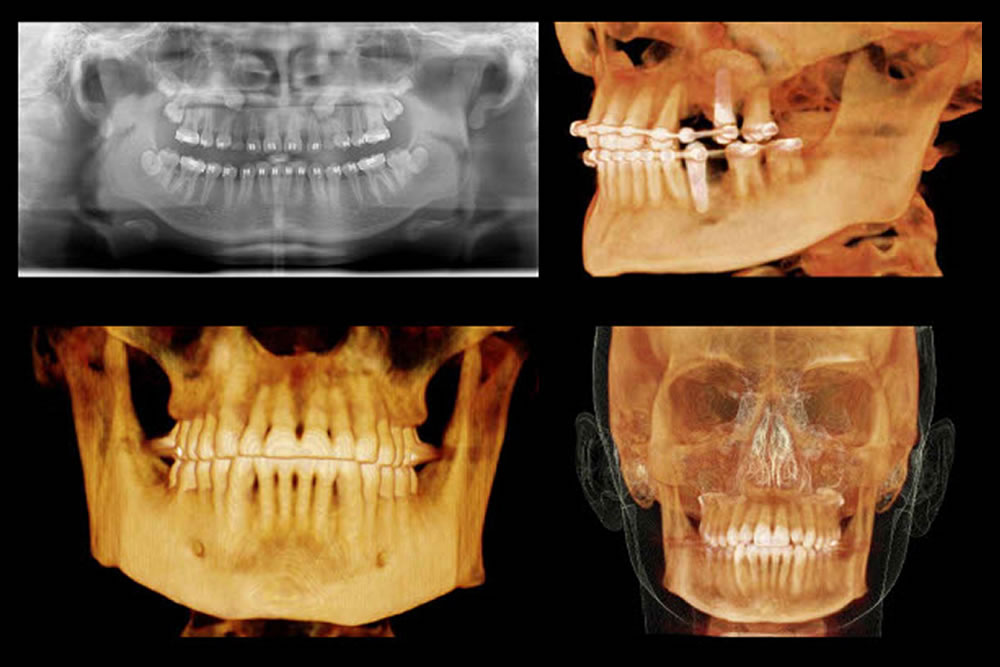

歯科用CTによる精密検査

インプラント治療の安全性を高めるためには、事前の検査が重要です。当院では歯科用CTによる三次元的な診断を行い、顎骨の状態や神経の位置を把握したうえで、リスクを抑えた治療計画を立案いたします。